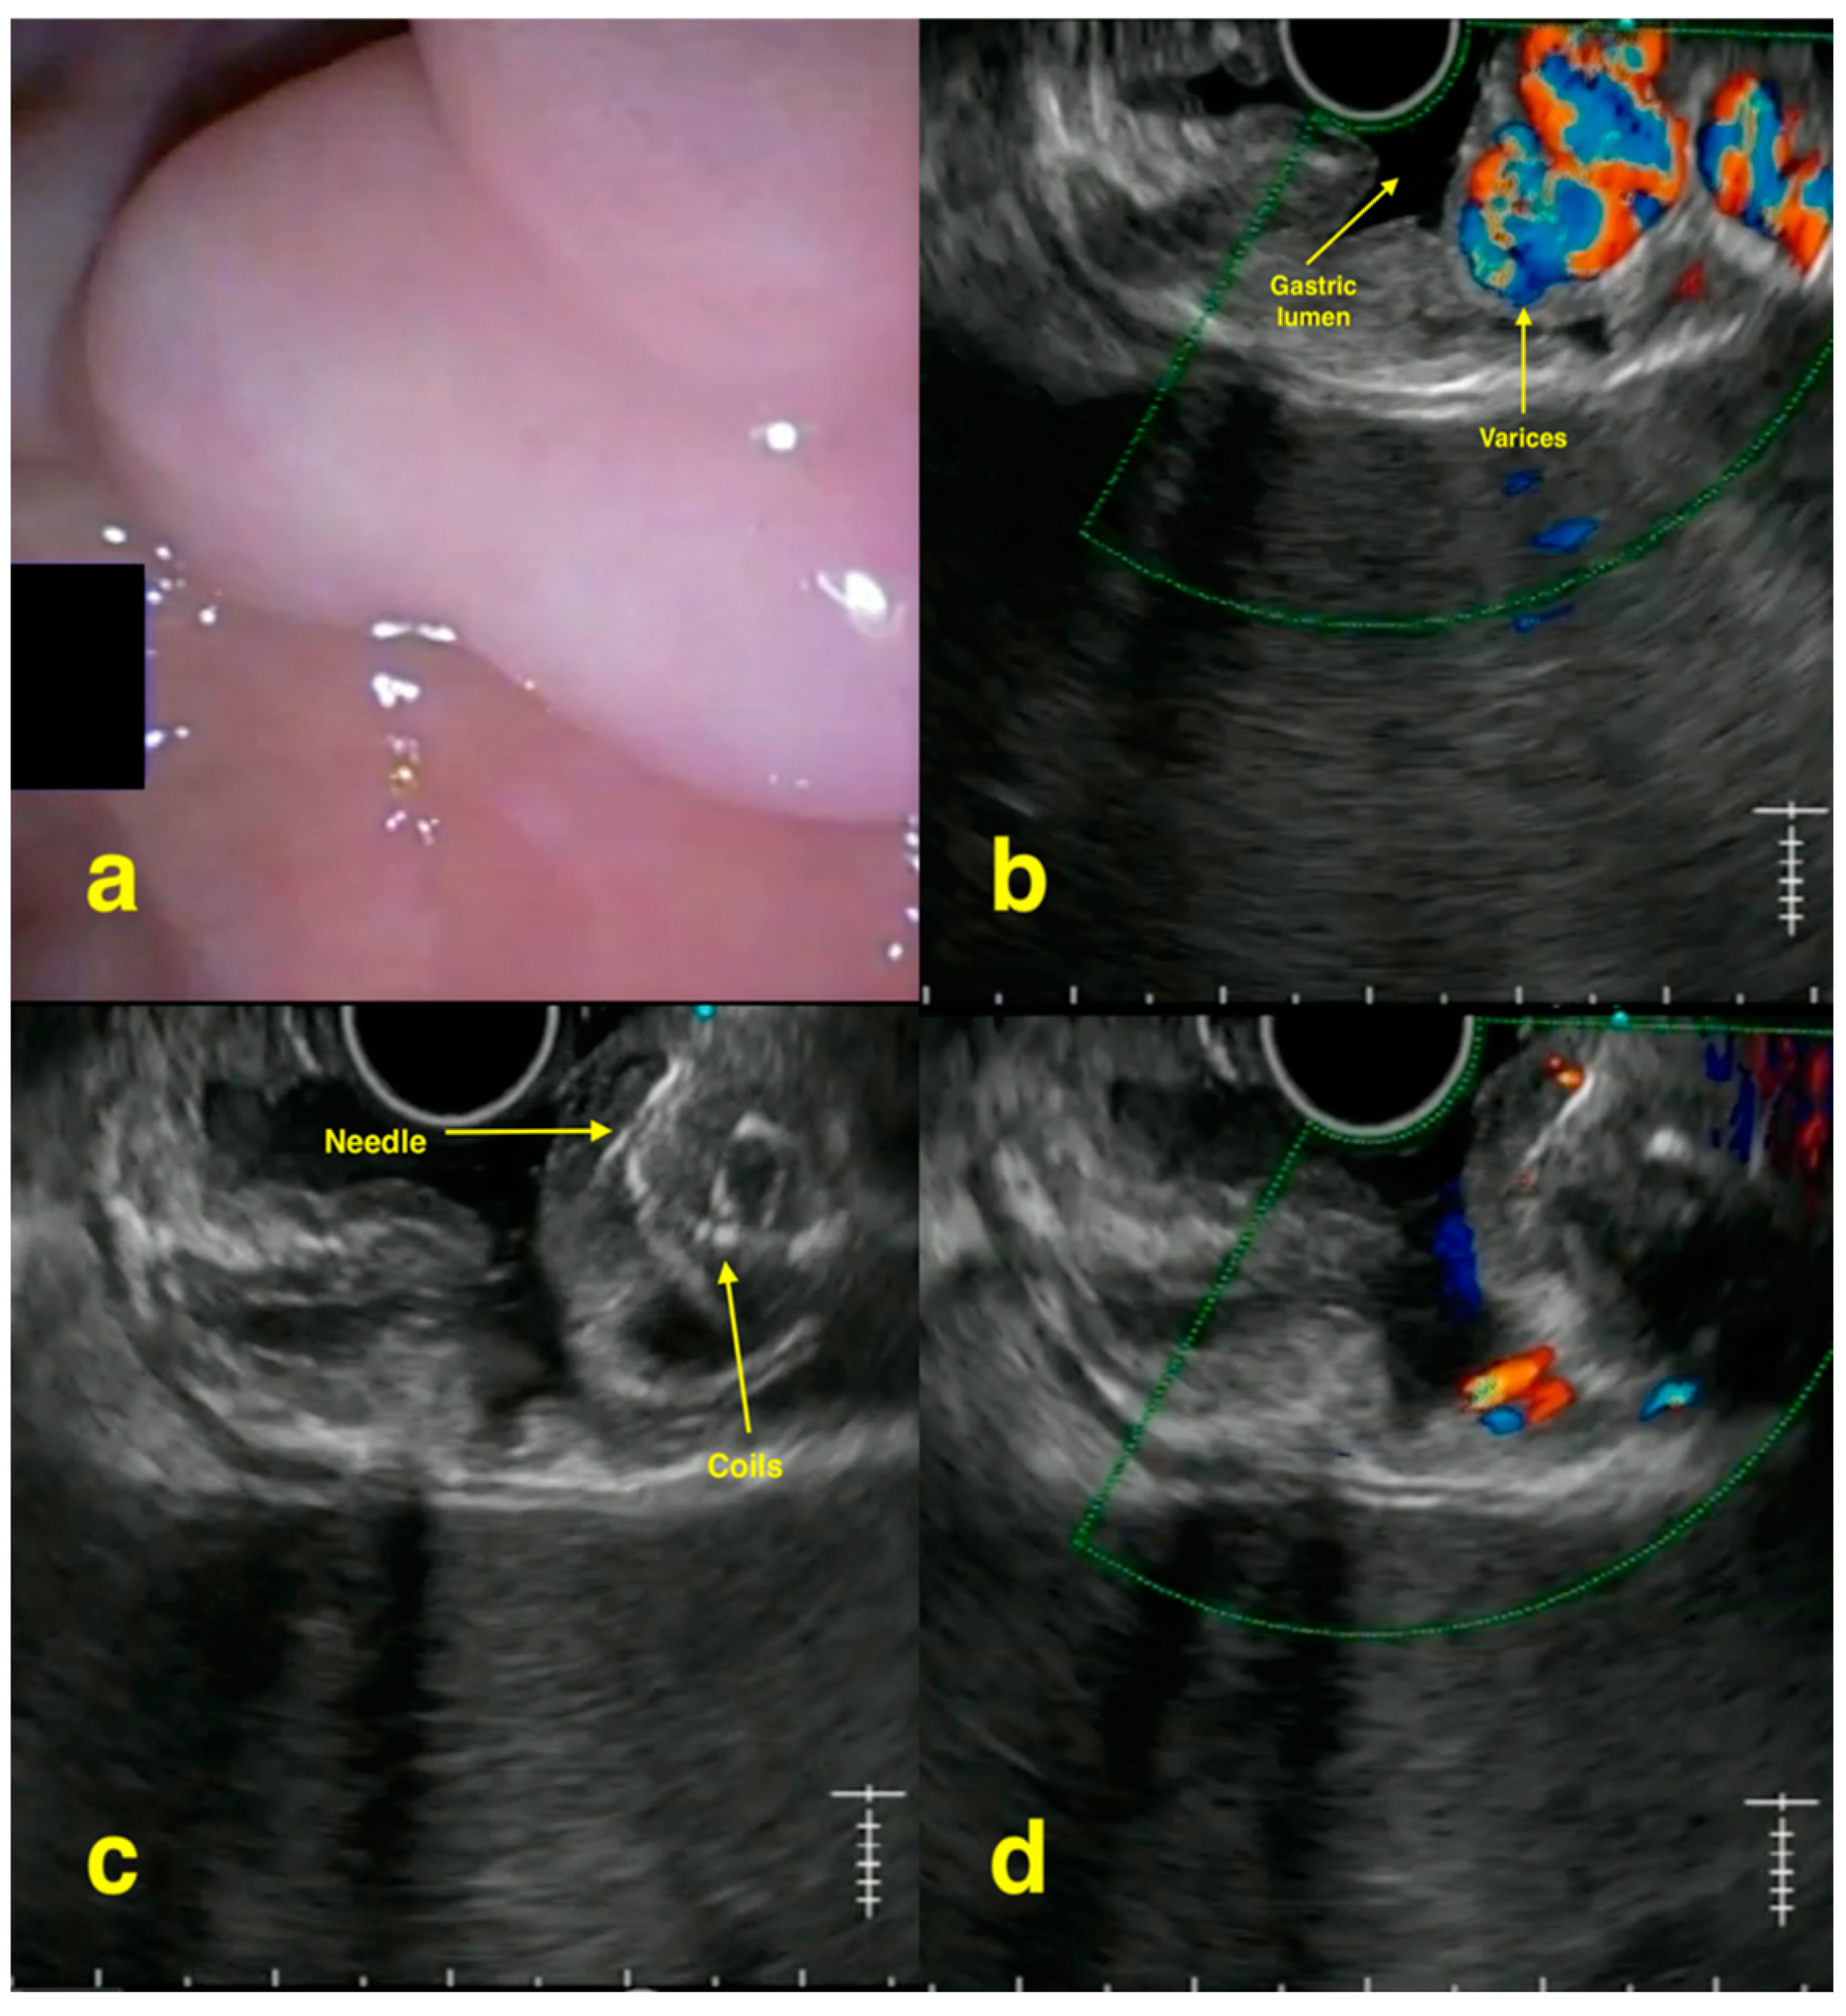

- Chavan, R.; Baraldo, S.; Patel, N.; Gandhi, C.; Rajput, S. Technical tips for EUS-guided embolization of varices and pseudoaneurysms. VideoGIE 2023, 9, 211–219. [Google Scholar] [CrossRef] [PubMed] [PubMed Central]